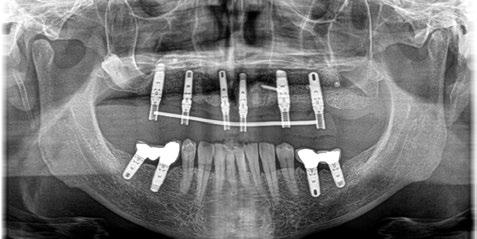

-Estudio radiográfico inicial (ortopantomografía y radiografías periapicales) (Figura 2).

Figura 2. Ortopantomografía inicial.

25, 26, 28, 37, 38, 47 y 48. Presentaba corona desajustada en 13 con extensión en 12, implantes en 35-36, 45-46, con coronas ferulizadas en 35-36, 45-46, y dientes anteriores superiores con enfermedad periodontal Grado IV.

3. Exploración de tejidos duros

En la exploración radiográfica (OPG, CBCT) observamos la existencia de pérdida ósea interproximal, lesión apical a nivel de la raíz mesial del 27 y el cordal del primer cuadrante incluido y neumatización sinusal del primer y segundo cuadrante.

En el CBCT observamos pérdida ósea posterior superior debida a la neumatización de los senos maxilares izquierdo y derecho. También podemos observar disponibilidad ósea apical suficiente en dientes antero-superiores para la realización de una Implantología inmediata y corticales vestibulares y palatinas conservadas.

Figura 27. Ortopantomografía del provisional atornillado en boca para verificar ajuste.

ortopantomografía de verificación del ajuste pasivo de todos los implantes. Por último, tapamos las chimeneas con teflón y resina provisional y se chequeó nuevamente la oclusión, dando nuevamente las instrucciones de higiene y mantenimiento de la prótesis provisional (Figuras 24-27).